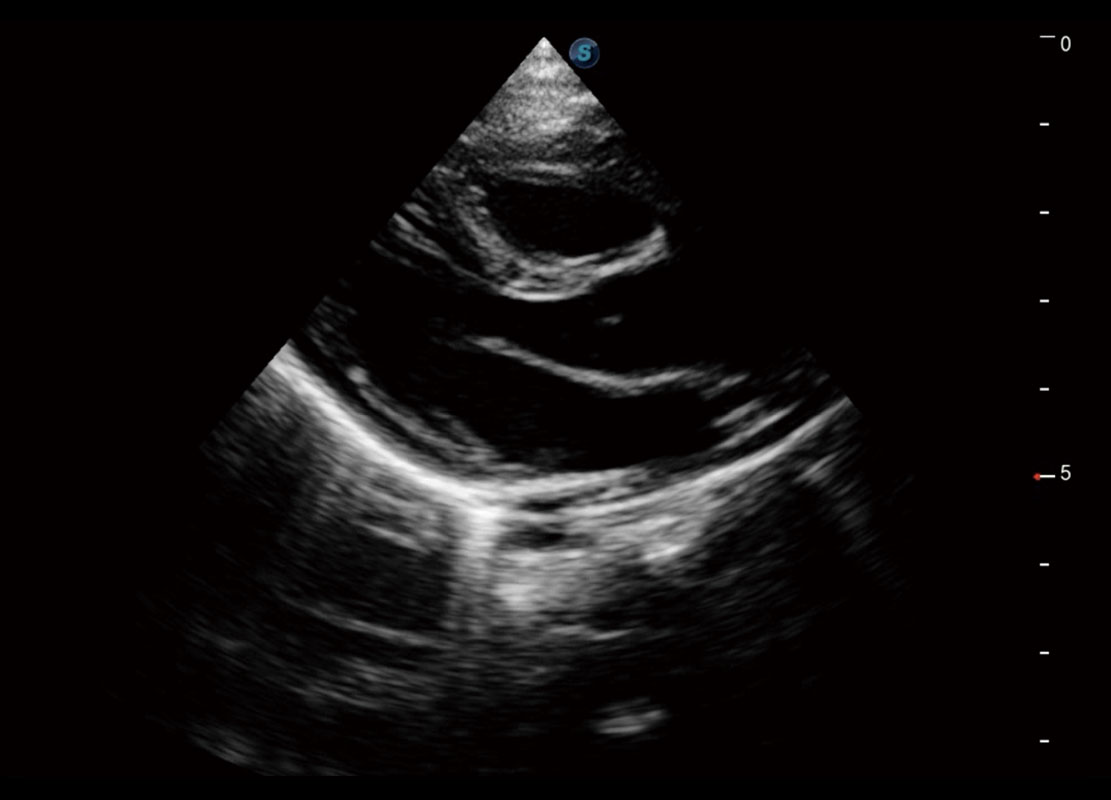

• 新生儿心脏

乳腺超声 / 新生儿

P60搭载宽频带线阵探头、宽景成像、弹性成像技术,为您提供乳腺应用方案。P60支持高频相控阵探头、线阵探头、腹部高频探头、腹部微凸探头等,丰富的探头群搭载敏感的彩色血流成像,适用于新生儿多种脏器检测要求,满足新生儿筛查需求。